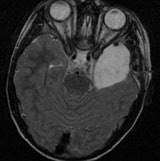

Incidental findings -- also known colloquially as "incidentalomas" or findings that are discovered unintentionally -- are on the rise around the world. Only about 1% of these findings are harmful to the patient, but still, in 1% of patients they're a problem, so what's a radiologist to do about them?

Incidentalomas are a relatively new phenomenon that account for approximately 15% to 20% of all findings. This is primarily because, for instance, the number of CT scans has shot up from around 3 million in 1980 to around 80 million in 2012 over the past decade in the U.S., he added. Due to the population increasing and getting older, the frequency of incidentalomas is only going to rise, he added. Beyond that, there's also a sophistication issue; the technology around the world has become more sensitive, so radiologists see things today they didn't 15 years ago.